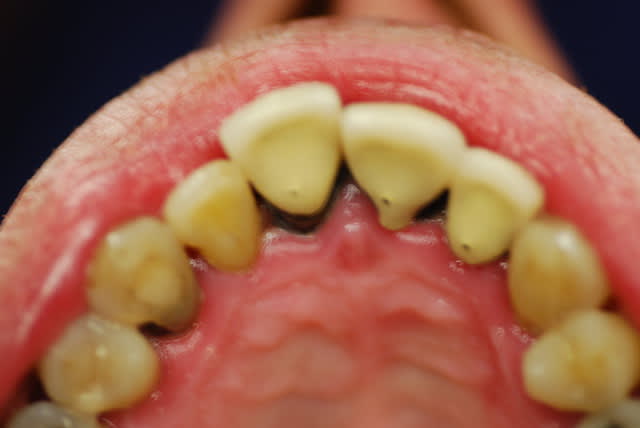

Je viens de revoir le patient et je peux vous apporter quelques précisions ainsi que des photos( désolé si la qualité n'est pas parfaite).

Patient de 45 ans, fumeur, motivé mais ne pouvant se payer d'implants.

Il a déjà vu plusieurs confrères qui lui ont proposé uniquement ( selon ses dires) une solution implantaire pour 12-11-21-22-23. Il souhaite du fixe...

En ce qui concerne la paro, la 12 est en mobilité stade 2, la 22 en stade 1 les autres étant non mobiles. Le sondage de 12 à 22 est de 3 mm, sauf en mésiale de 12 ( 6mm). La gencive est inflammatoire ( logique à la vue de l'inadaptation des couronnes, et des caries radiculaires).

Je pense lui proposer la solution du bridge avec 13,11,21,22, 24,25., même si la 13 est saine... Je prévoyais de reprendre l'endo de 22 mais la taille du tenon et sa longueur m'ont refroidi, peut être qu'une chir endo et obturation à rétro serait plus appropriées... Je prévois bien sur un surfaçage ainsi qu'un assainissement paro, une fois le bridge provisoire en place.